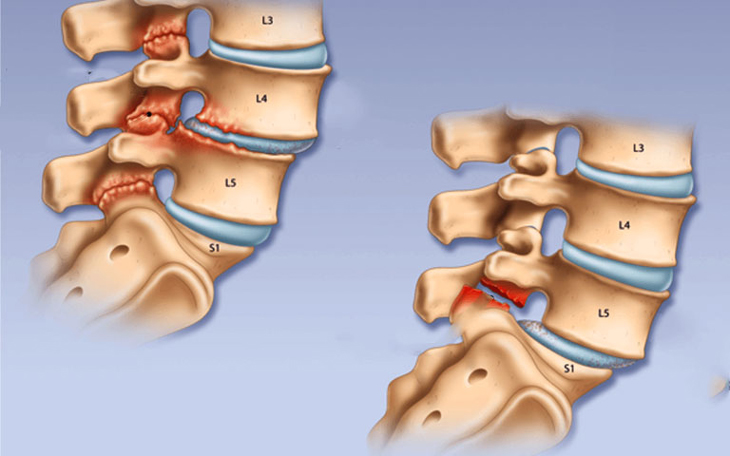

Trượt đốt sống Điều trị trượt đốt sống bằng phương pháp nội khoa hoặc phẫu thuật

Điều trị bằng phẫu thuật trong các trường hợp: trượt đốt sống có tổn thương rễ thần kinh; có đau cột sống thắt lưng điều trị nội khoa nhưng không đỡ; trượt đốt sống tiến triển ngày càng nặng. Phẫu thuật ghép xương làm liền xương vững chắc giữa các đốt sống, loại bỏ chuyển động bất thường giữa các đốt sống kém vững.